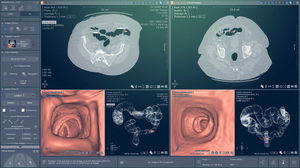

... Análisis rápido. Comunicación optimizada El módulo CS Airway está diseñado para simplificar el análisis de las vías respiratorias a través de vistosas representaciones en 3D. En unos pocos segundos, el módulo ...

Carestream Dental

... Benefíciese de aplicaciones clínicas especialmente diseñadas para realizar sus exámenes de oncología, hígado, próstata, colon o grasa abdominal en cuestión de minutos. Flujos de trabajo clínicos dedicados que ofrecen una amplia gama de ...

Intrasense

... Benefíciese de aplicaciones clínicas especialmente diseñadas para realizar sus exámenes de oncología, hígado, próstata, colon o grasa abdominal en cuestión de minutos. Flujos de trabajo clínicos dedicados que ofrecen una amplia gama de ...

Intrasense